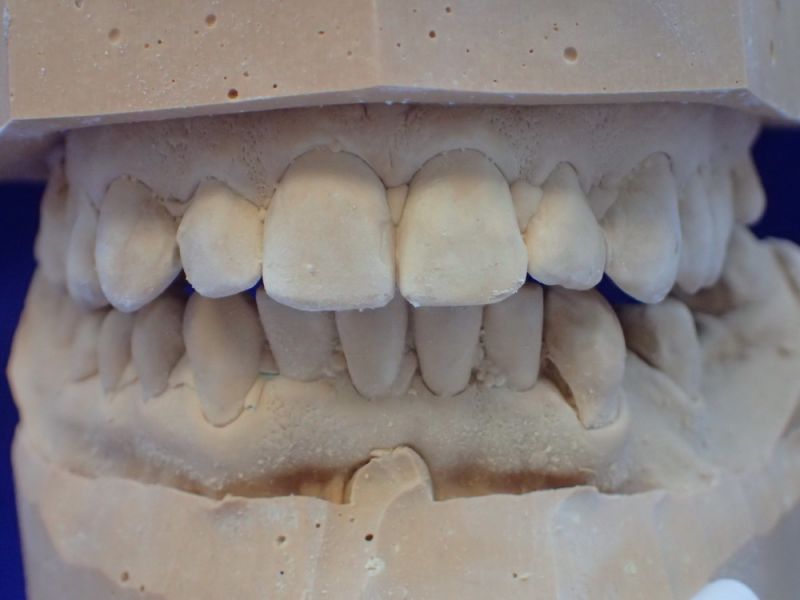

2. Herstellung und Eingliederung eines adjustierten Aufbissbshelfs

Erkennbar ist die massive Abweichung der habituellen Bisslage von der neuromuskulär zentrierten Bisslage.